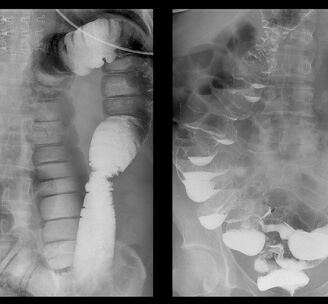

Більшість хвороб можуть призвести до смерті, тому боятися лише раку – це неприпустима помилка. Подивіться знімки органів людей, у яких все почалося з неприємного запаху з рота, сверблячки та кров'янистих виділень із анального отвору відповідно, а закінчилося доповіддю патологоанатома.